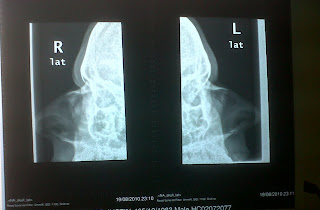

nose broken bone septum xray bones spot august dislocated apparently worse having because than which